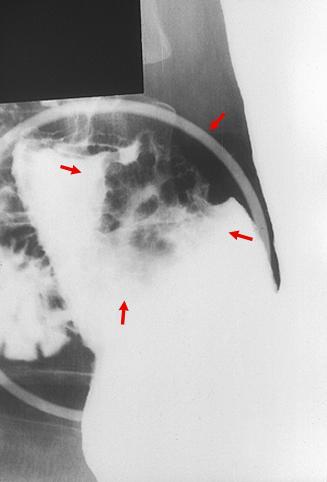

Criteria of Hist.ClassificationMalignant epithelial tumor/Adenocarcinoma

LocationStomach/Antrum

Technique, MethodX-ray

Macroscopic TypesType 0/IIa (IIa+IIc) Superficial elevated and depressed type

Size25 - 29

Depth of Tumor Invasionmucosa